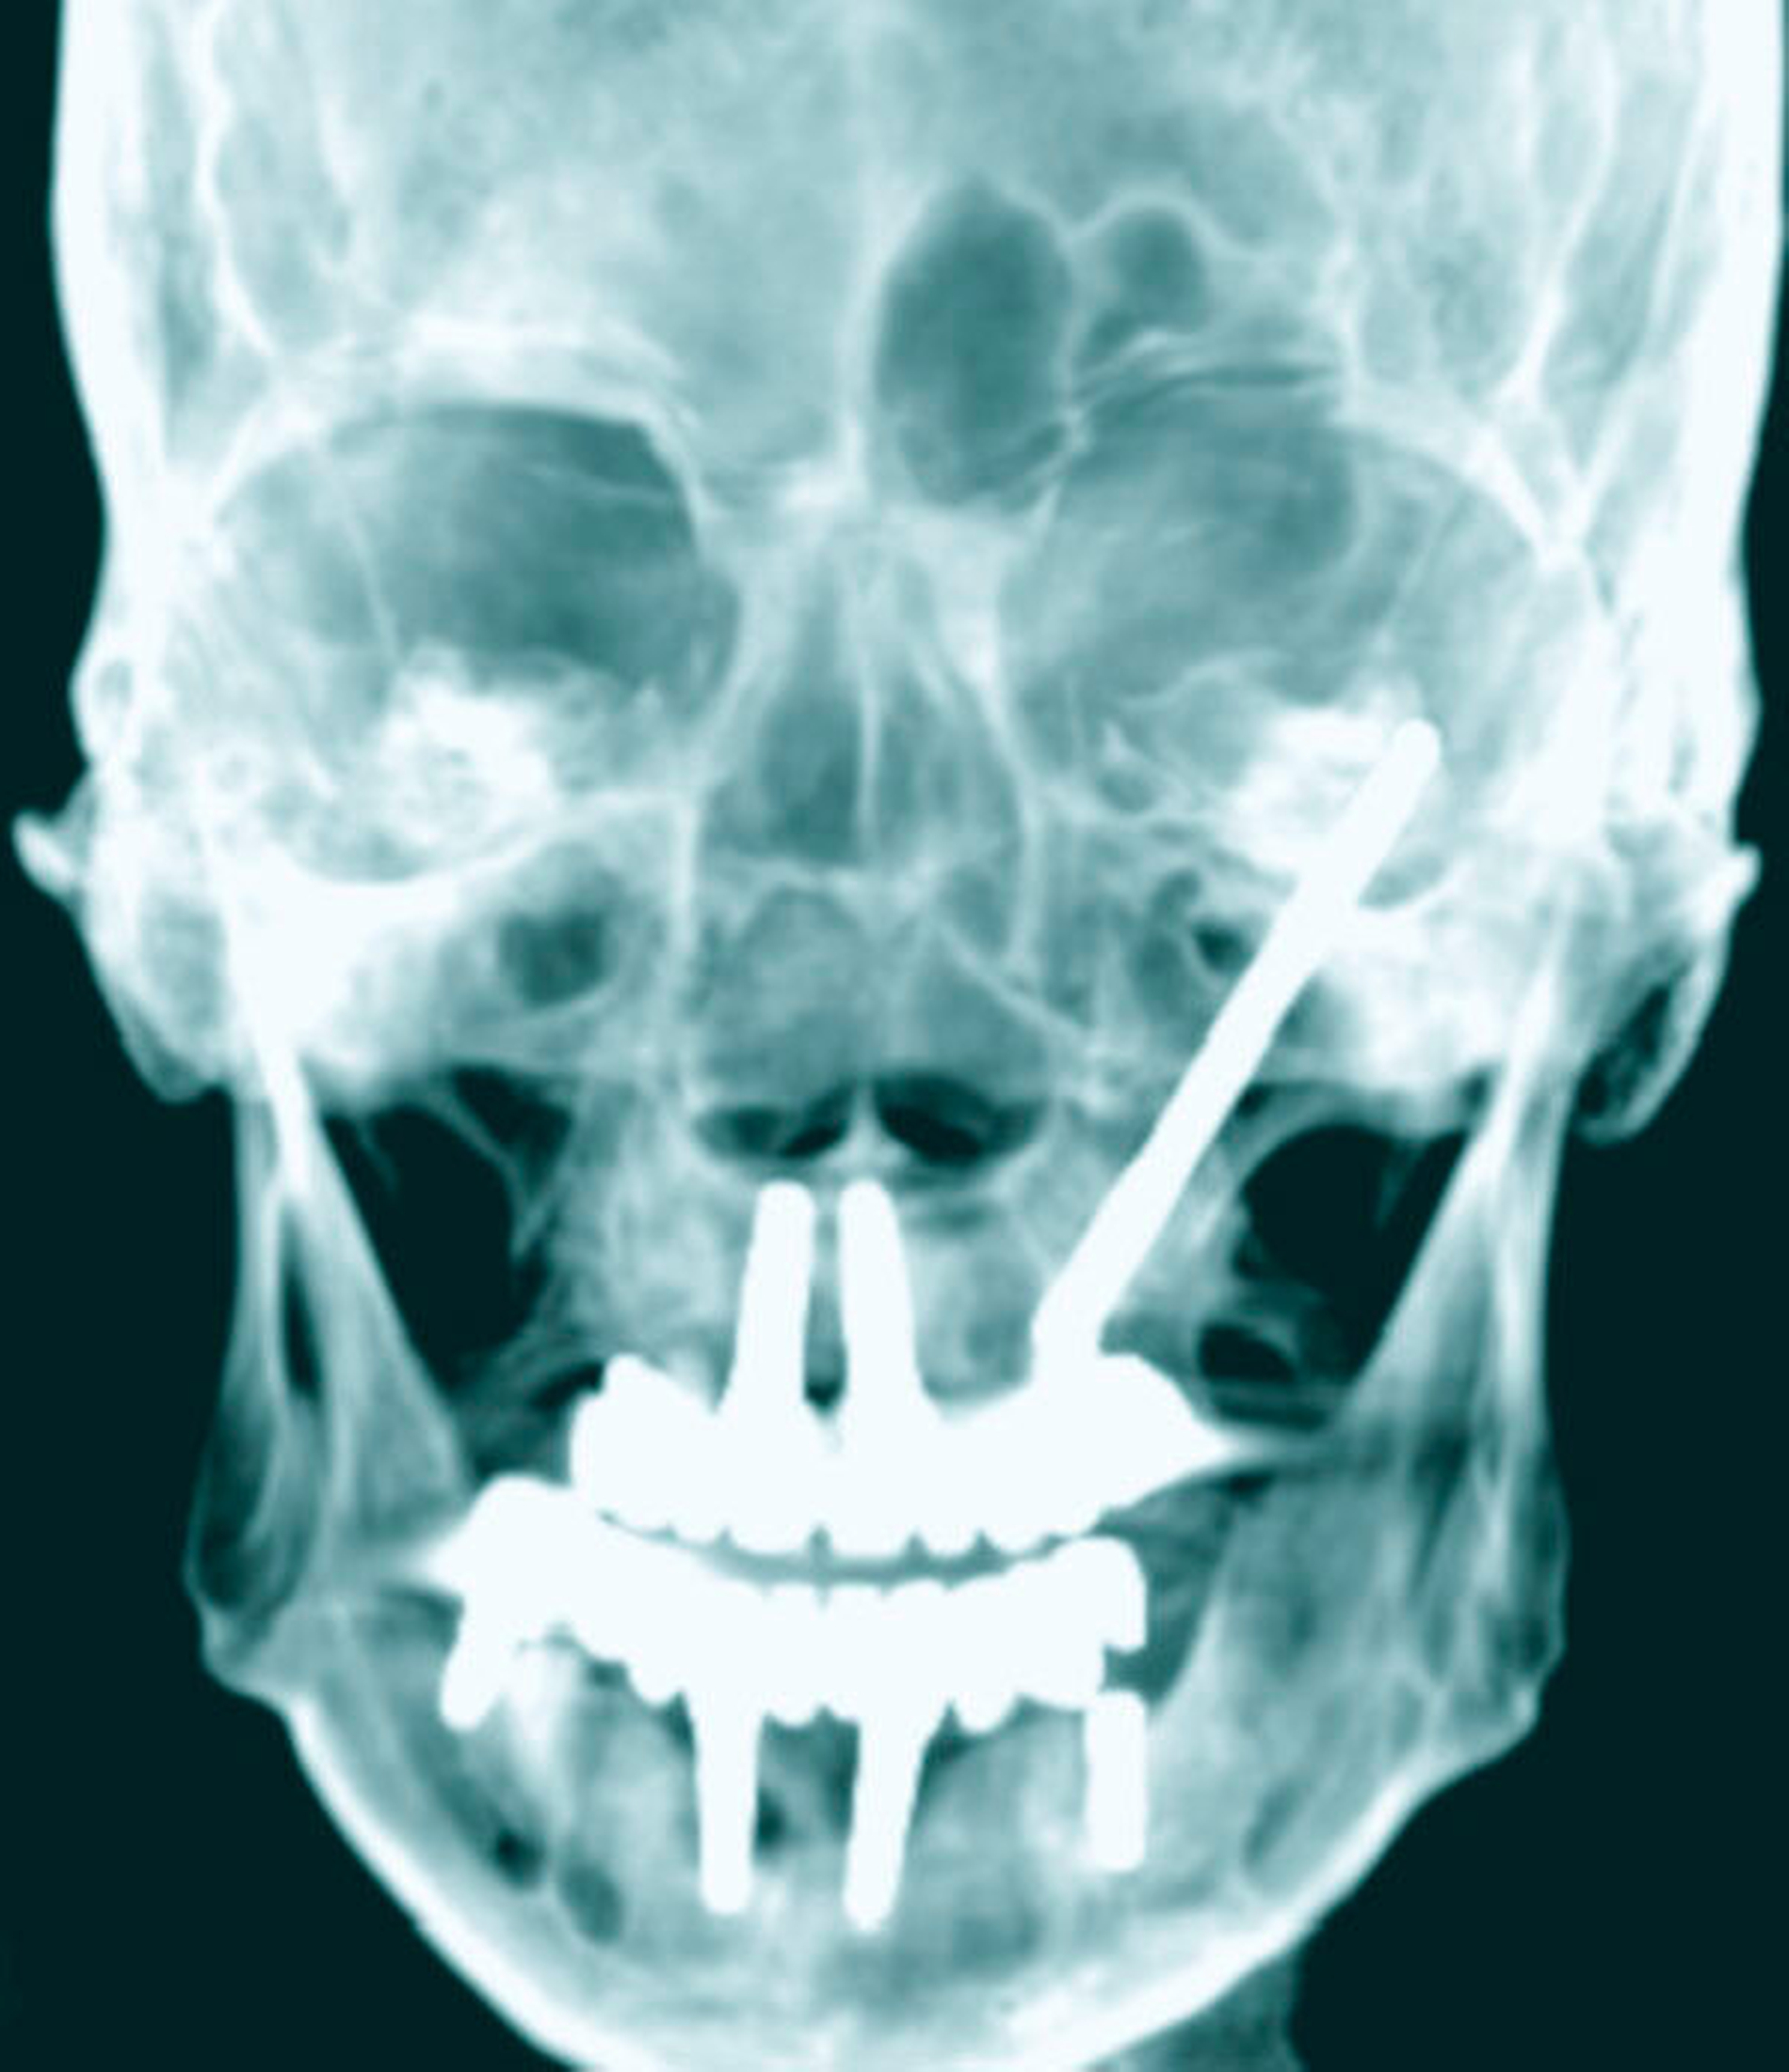

Wegen der unklaren Genese der akuten entzündlichen Veränderungen in der Orbital- und in der Periorbitalregion wurde eine CT- Diagnostik des Schädels mit Kontrastmittelgabe zum Ausschluss einer akuten retrobulbären Raumforderung veranlasst. Hierbei fand sich ein hochgradiger Verdacht auf eine Abszedierung in der rechten Orbita mit dem klinischen Bild von Protrusio bulbi und entzündlicher Mitreaktion der Augenmuskeln M. rectus lateralis und M. rectus inferior. Diese Veränderungen waren auch der Grund für die Weichteilschwellung am Unterlid. Ein intraorbitales Hämatom ließ sich ausschließen.

Zur weiteren Abklärung erfolgte nach zweidimensionaler Beurteilung die dreidimensionale Rekonstruktion der CT-Daten. Hierbei kamen die röntgenopaken Implantate im Kiefer sehr gut zur Darstellung und konnten in Bezug auf deren anatomische Lage beurteilt werden. Im atrophen Ober- und Unterkiefer zeigte sich ein mittelgradiger horizontaler Knochenabbau mit vertikalen Einbrüchen an allen Implantaten. In der rechten Maxilla regio 016 bestand nach Explantation eines rechtsseitigen Zygoma-Implantats ein circa 2 cm großer Defekt, der, aufgrund der verdrängten Weichgewebe und Lufteinschlüsse sicher bis in die mittlere, zentrale Orbita reichte.

Als auffälliger Nebenbefund fand sich auch auf der linken Seite ein 60-mm-Zygoma-Implantat, das 17 mm in die linke Augenhöhle ragte. Neu aufgetretene Veränderungen oder Behinderungen in diesem Bereich waren vom Patienten subjektiv nicht wahrgenommen worden, die Implantation selbst lag bereits zehn Jahre zurück.